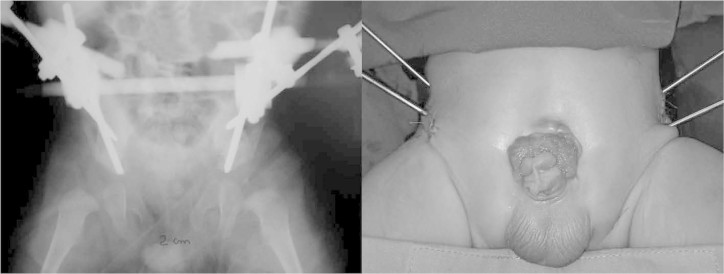

This patient underwent bilateral anterior pelvic osteotomy with placement of an external fixator in October 2007, subsequent to the procedure to close and repair the cloaca, but concomitantly to the repair to the epispadia that was performed (Figure 7). A reduction in the diastasis to 1.0 cm was achieved in the immediate postoperative period. This procedure again had the technical difficulty of lack of an image intensifier, which especially added difficulty to performing the vertical osteotomy, which was slightly oblique instead of vertical and parallel to the sacroiliac joint, as is recommended for the technique (Figure 8). The lack of intensifier also increased the duration of the operation because of the simple radiographs produced intraoperatively.

Figure 7.

Patient just after placement of the pins and before correction of the epispadia.

Figure 8.

A) Left: radiograph produced during the immediate postoperative period, showing reduction of the diastasis to 1.0 cm and slightly oblique positioning of the osteotomies parallel to the sacroiliac joints. B) Right: patient during the postoperative period, showing the external fixator and the correction of the epispadia.

The patient remained in hospital for two weeks. No skin traction was used, but only resting in bed. An external fixator was used for eight weeks. No postoperative complications were presented.